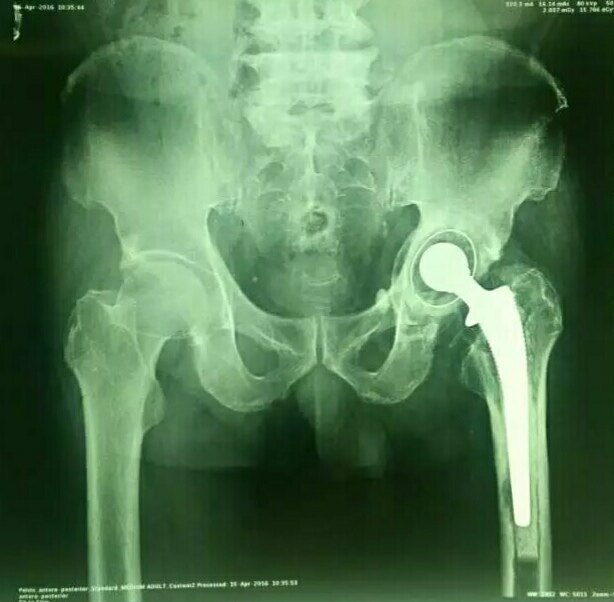

骨水泥型全髋关节置换术后10年松动,用生物型

614x602 - 45KB - JPEG

请问这个髋关节是用生物型还是骨水泥好?

639x360 - 38KB - JPEG